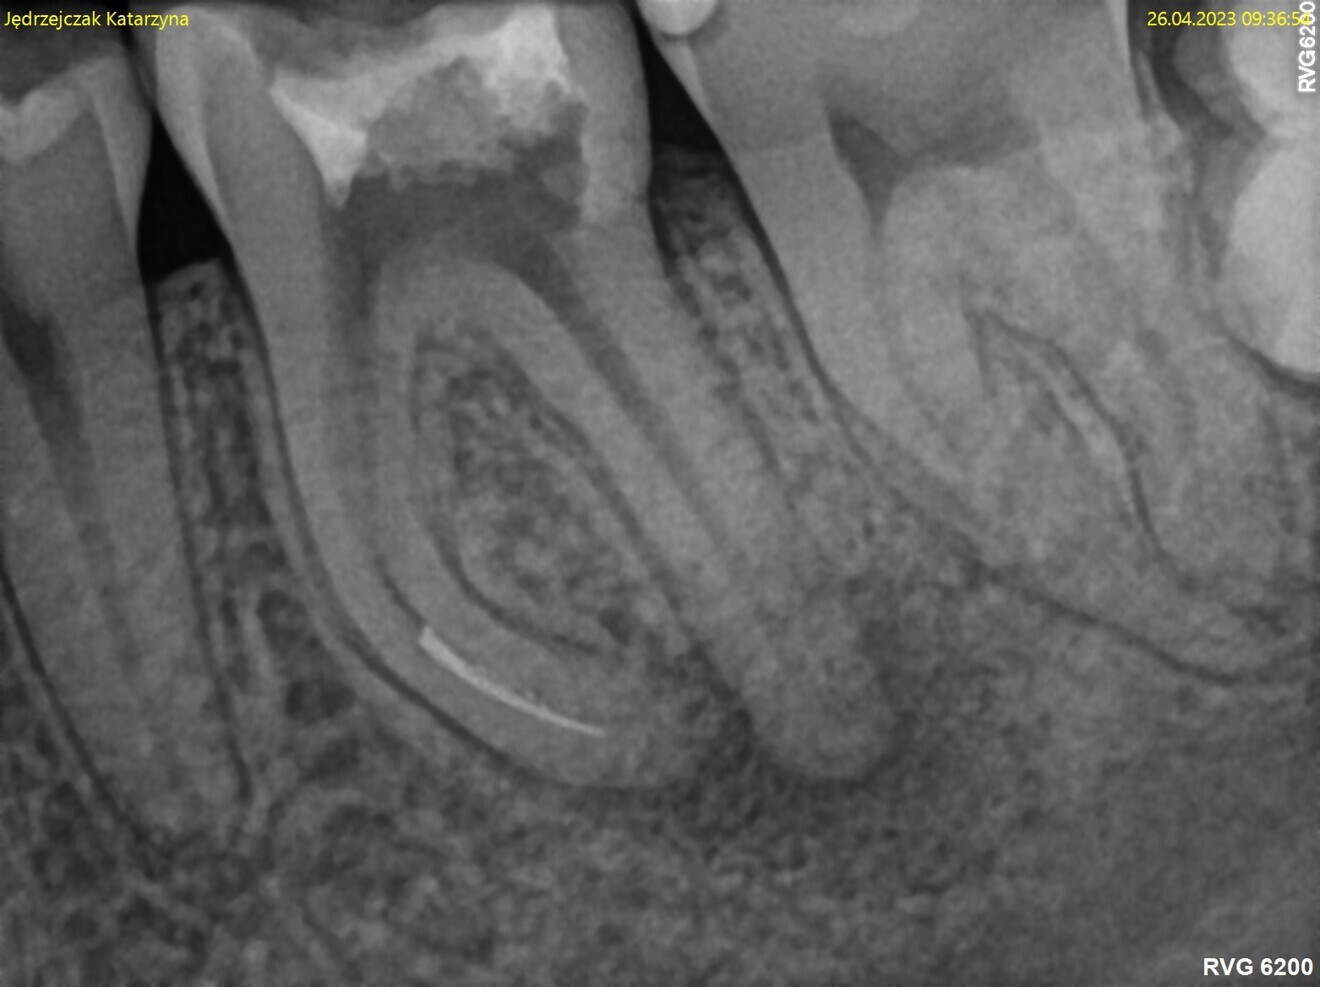

Fig. 1: Pre-op radiograph. Periapical lesion and broken file visible.

The periapical radiograph and the CBCT scan revealed that the file had broken far beyond the curvature in the mesiobuccal canal and below the junction with the mesiolingual canal. Also, a periapical lesion was visible around the apices of the mesial and distal roots (Figs. 1–3). The length of the file was approximately 5 mm. Bypassing the file through the mesiolingual canal would have been a risky procedure because it may have caused the fracture of the second instrument and the obturation may also have been very challenging. Thanks to SWEEPS technology and a bioceramic sealer, an alternative approach could be taken. After administering anaesthesia and placing a dental dam, the temporary restoration was removed (Figs. 4 & 5). The pulp chamber was rinsed with 5.25% sodium hypochlorite and the irrigant activated with ultrasonics. After cleaning the chamber of the tooth, the dental dam and clamp were rinsed with water and dried and flowable dental dam was placed to seal the tooth and enlarge the space in the pulp chamber for the laser-activated irrigation (Fig. 6). Activation was performed with the SkyPulse laser (Fotona). The AutoSWEEPS mode was chosen. The power of activation was set to 1 W. The flat SWEEPS 300/20 fibre tip was used (Fig. 7). The tip was placed slightly below the orifice of the mesiobuccal canal for the majority of the irrigation with sodium hypochlorite. After 120 seconds of activation with sodium hypochlorite, the tip was placed in the pulp chamber to activate the sodium hypochlorite in all the canals simultaneously for 30 seconds. This procedure was continued for 30 minutes. Only the distal canal was shaped with rotary files, up to size 40/.04. Both mesial canals remained the same size as they were before the file broke during the primary treatment. Finally, the canals were flushed with EDTA activated with AutoSWEEPS at a power of 0.4 W, and sodium hypochlorite was activated for three cycles with AutoSWEEPS at a power of 0.6 W and with a 30-second break for the resting phase. The irrigant flow between the mesiobuccal and mesiolingual canals was rapid, indicating that obturation could be performed.